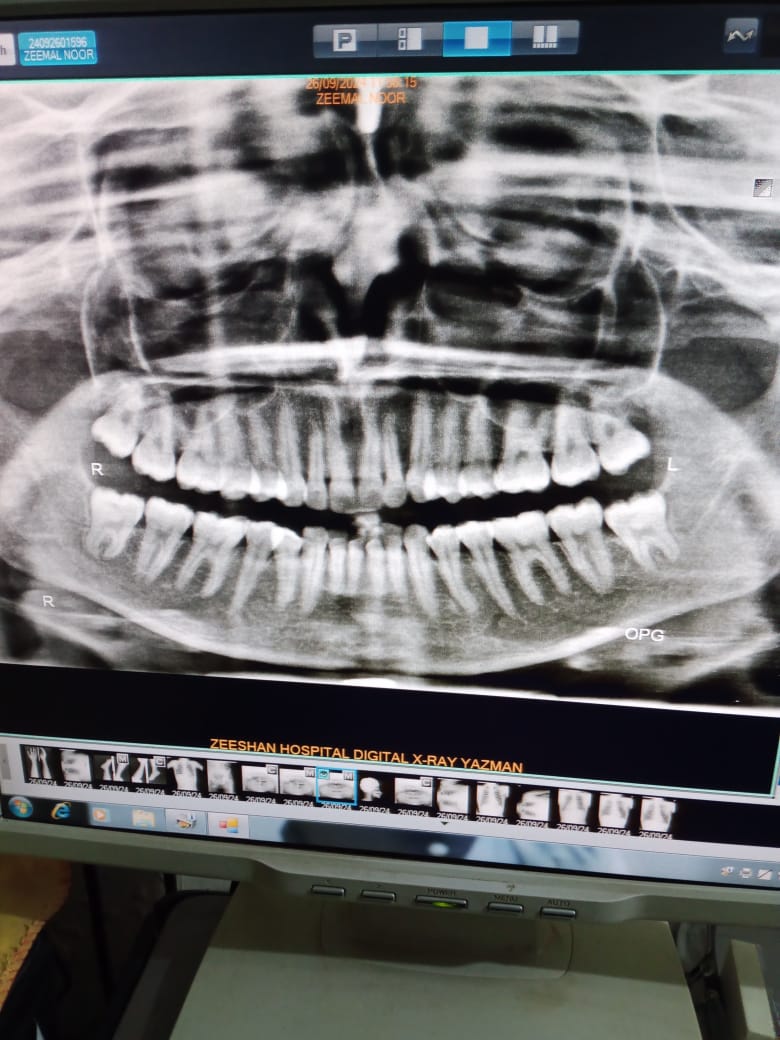

I have a misalignment with my teeth being a bit forward. Could you please provide information on the cost of aligners and braces? Also, which option would be more suitable for correcting this issue?

I think your case is surgical orthognathical case .needs ceph analysis visit your nearest dental hospital

need more analysis like lateral ceph and cast model then only give complete treatment plan and cost plz visit us or at your nearest Orthodontist